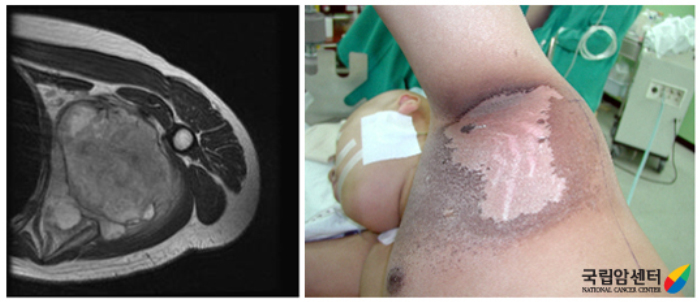

[ 오른쪽 대퇴부 지방육종 환자의 사진 ]

[ 좌측 액와부에 육종을 수술 전 방사선 치료 후 수술적 절제를 위한 모습 ]

[ 절제해낸 지방육종의 단면과 병리 ]

[ 오른쪽 견갑부 주위 악성섬유성조직구종 환자의 수술적 절제술 사진 ]

[ 오른쪽 서혜부에 재발성 평활근 육종 환자의 사진과 광범위 절제술후 사진 ]